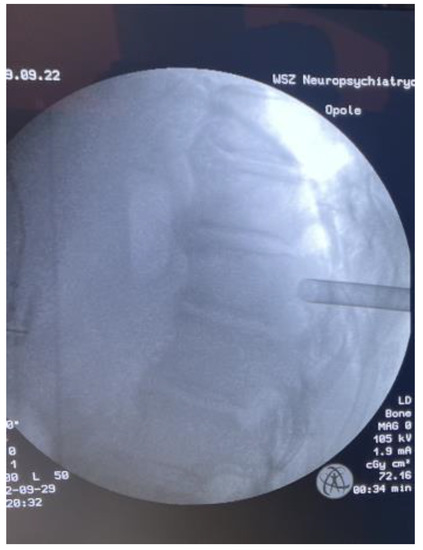

Fully Endoscopic Spine Separation Surgery in Metastatic Disease—Case Series, Technical Notes, and Preliminary Findings

2. Materials and Methods

3. Results